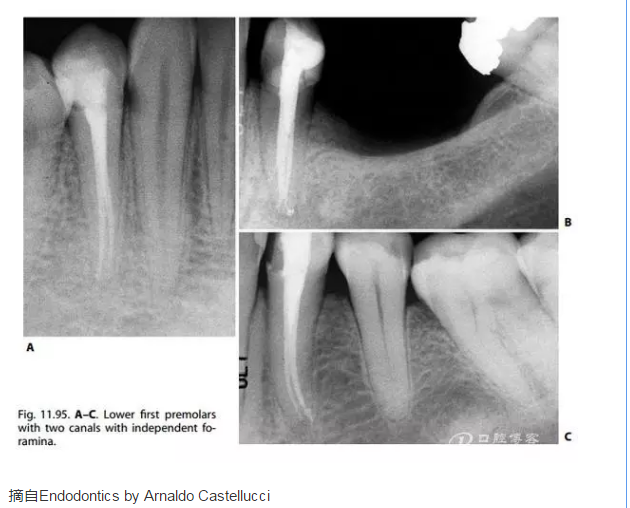

書中特別強(qiáng)調(diào),調(diào)查表明有3個(gè)根管及“C”型根管的可能性。并認(rèn)為最復(fù)雜的情景就是單根管但在根尖1/3分叉為雙根管的病例。如下圖所示。Baisden, Kulid, Weller 報(bào)告認(rèn)為有一個(gè)根管兩個(gè)根尖孔的下頜第一前磨牙有14%是“C”型根管。

摘自Endodontics by Arnaldo Castellucci